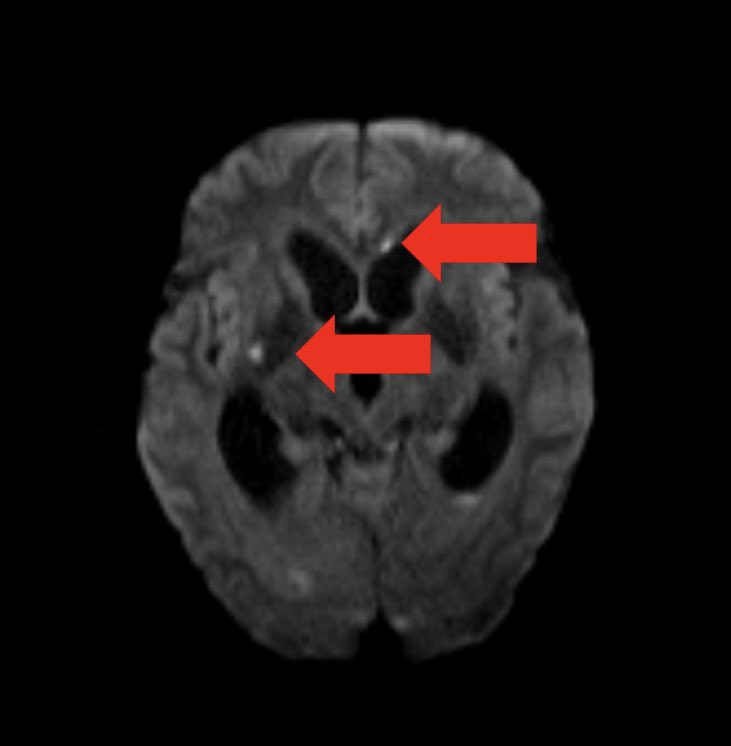

So it seems they have a florid MRSA infection of the ๐Ÿง  leading to the ๐Ÿง ๐Ÿ’ง. But MRI of the ๐Ÿง  also shows small ischemic strokes in multiple territories (DWI shown)

7/